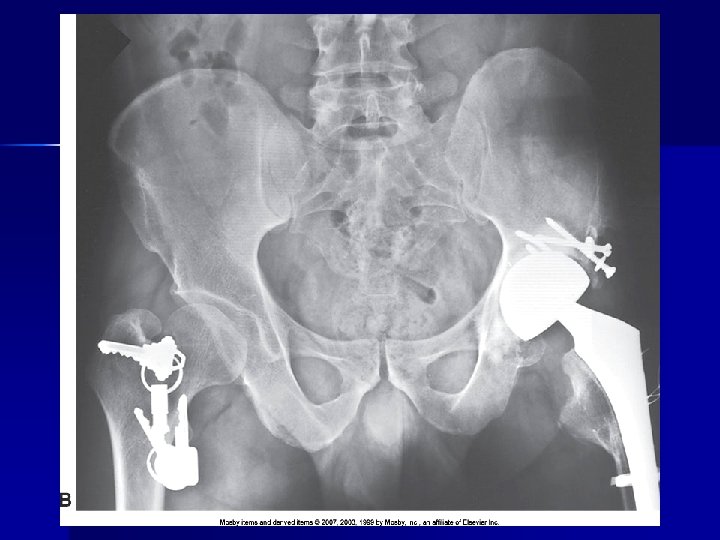

Pt clothing

PATHOLOGY NOT ARTIFACT